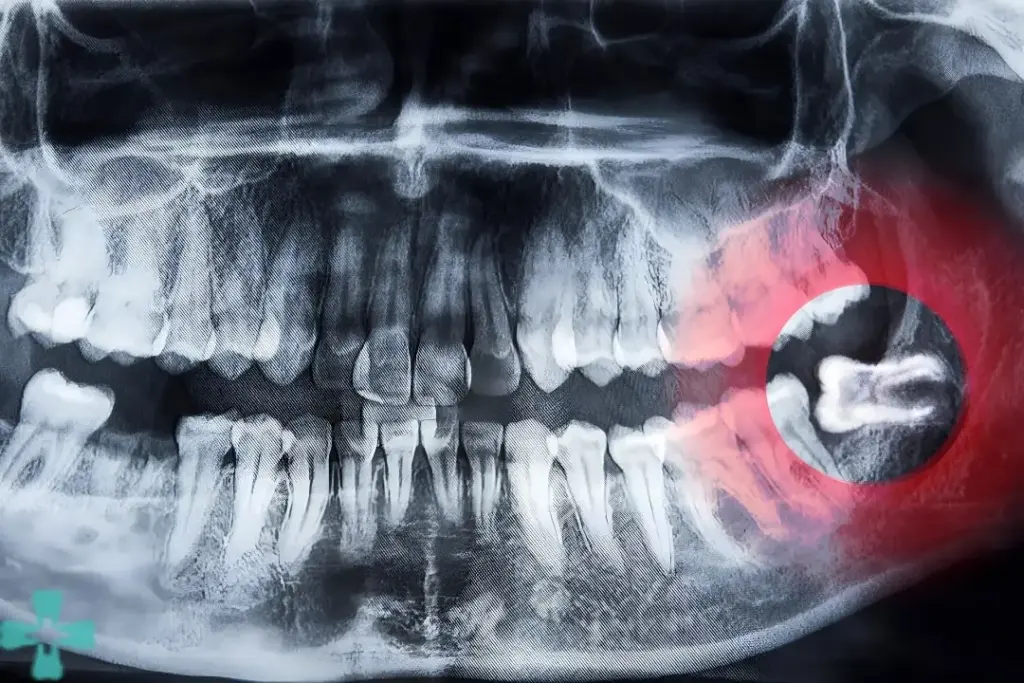

Dental X-ray showing an impacted lower wisdom tooth pressing against the adjacent molar

Panoramic dental X-ray showing an impacted lower wisdom tooth pressing against the adjacent molar

Wisdom teeth often cause problems because they do not fully erupt or come in at improper angles. When this happens, they can trap bacteria and debris beneath the gums.